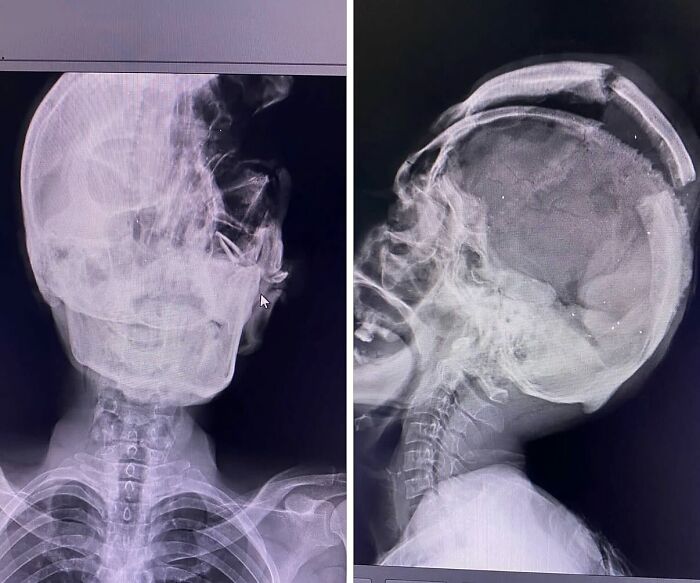

#9 Extreme Case Of Hydrocephalus In A Pediatric Patient

Hydrocephalus is a pathology characterized by dilation of the cerebral ventricles, normally caused by the obstruction of the flow of cerebrospinal fluid (CSF), or by an imbalance between its production and absorption, in addition there is inflammatory response, neuronal damage and destruction of periventricular axons.

Hydrocephalus is cataloged in two ways. Depending on the origin, it can be congenital or acquired; and in relation to the CSF flow, this pathology is classified as communicating (i.e. CSF can exit the ventricular system, but the fluid is not absorbed readily, or there is too much fluid to be absorbed) or non-communicating (i.e. CSF cannot exit the ventricular system, and thus there is obstruction to CSF absorption, resulting in an increased pressure inside the brain). Symptoms of hydrocephalus may include an unusually large head with thin, transparent scalp, bulging forehead with increased spaces between the bones of the skull (fontanelles), and a downward gaze.

The most common congenital cause is the obstruction or narrowing (stenosis) of the cerebral aqueduct — the long, narrow passageway between the third and fourth ventricles of the brain. It can also be caused by infections, hemorrhage or a tumor.

The condition is pretty rare and can be easily detected early in pregnancy by ultrasound which does not necessarily shows the obstruction but detects an abnormal collection of fluid.

These kids are treated after birth by either inserting a shunt, small flexible plastic tube that diverts excess CSF from the brain to another part of the body where the fluid can be reabsorbed; or by an endoscopic ventriculostomy, where a small hole is made in the floor of the third ventricle, allowing the CSF to bypass the obstruction and flow toward other areas where reabsorption can happen.